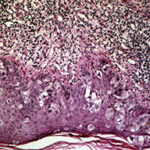

PATHOLOGY The intraepidermal adenocarcinoma of EMPD and MPD has a similar histologic appearance. There are groups, clusters, or single cells within the epidermis that show nuclear enlargement with atypia, prominent nucleoli, and well-defined ample cytoplasms . Intercellular bridges are absent. The cells can be within all levels of the epidermis and can compress but preserve the basal layer without junctional nest formation. The cells can extend into the contiguous epithelium of hair follicles and sweat gland ducts. Acanthosis, hyperkeratosis, and parakeratosis are often present. These cells have a “pagetoid” appearance and simulate other intraepidermal malignancies, including melanoma, pagetoid squamous cell carcinoma in situ, mycosis fungoides, cutaneous adnexal carcinomas (sebaceous carcinoma, porocarcinoma, and others), Merkel cell carcinoma, Langerhans cell histiocytosis, and other epidermotropic cutaneous metastases. The cells of MPD and EMPD can be pigmented, which should not necessarily indicate they are melanocytic. Paget's cells have intracellular mucopolysaccharides, with EMPD having a greater amount of mucin as compared

Immunohistochemistry is a useful adjunct in making the correct diagnosis. Low-molecular-weight cytokeratin stains cytokeratin 7 (CK7) and anti-cytokeratin (CAM 5.2) are sensitive markers for both MPD and EMPD . They are not completely specific, however, with both Toker and Merkel cells showing CK7 positivity. The cells of MPD and EMPD may stain with carcinoembryonic antigen and epithelial membrane antigen. The most useful keratin markers for Paget disease are CAM 5.2 and CK7, as they stain more than 90 percent of Paget's cells but do not react with epidermal or mucosal keratinocytes.13,14 The cells of pagetoid squamous cell carcinoma in situ typically do not stain with CK7 and CAM 5.2. S100 and HMB-45 are useful markers to exclude melanoma, as both are typically negative in MPD and EMPD. CK20 positivity has been found more frequently in cases of secondary EMPD with underlying carcinoma as compared to those cases of primary intraepithelial EMPD (CK7+/CK20-).15 Gross cystic disease fluid protein-15 (GCDFP-15) is a marker for apocrine epithelium and is typically positive in primary EMPD not associated with underlying neoplasm. In contrast, GCDFP-15 is frequently negative in those cases of secondary EMPD with an associated malignancy.16 Mucin core protein (MUC) expression is useful in the diagnosis of MPD and EMPD.17 MUC1 positivity is noted in both MPD and EMPD. MUC2 expression is generally negative in primary EMPD, but may be expressed in those cases of secondary EMPD with an associated underlying gastrointestinal adenocarcinoma. MUC5AC is frequently positive in primary EMPD and less commonly noted in secondary EMPD or those cases of primary intraepithelial EMPD that becomes invasive. SPECIAL TESTS Diagnosis of MPD and EMPD should be accompanied by a thorough search for underlying malignancy. Mammography is indicated in all cases of MPD, with biopsy of any underlying breast mass. In cases of EMPD, workup is directed toward the possibility of an underlying gastrointestinal or genitourinary neoplasm. Imaging of the abdomen and pelvis, colonoscopy, barium enema, cystoscopy, intravenous pyelogram, chest x-ray and mammogram (for the rare association of EMPD and MPD), and blood work are appropriate tests. Some reports have suggested that positron emission tomography scans may be useful for cases of invasive EMPD to evaluate for lymph node involvement and metastases. COMPLICATIONS Failure to identify and adequately treat cases of MPD can lead to metastatic disease with a poor prognosis. EMPD, if left untreated, can become invasive with a less favorable outcome. PROGNOSIS AND CLINICAL COURSE Overall survival in patients with MPD is affected by lymph node status and the presence of an underlying breast mass. Patients with negative lymph nodes have been shown to have a 10-year survival rate of 75 percent to 95 percent, whereas those with positive lymph nodes have a survival rate of 20 percent to 45 percent.4 Patients with a palpable breast mass have a 5-year survival probability of 35 percent to 51 percent, as compared to 75 percent to 82 percent in patients without a palpable mass. The prognosis for primary EMPD confined to the epidermis is excellent with appropriate treatment. Careful monitoring for early detection of local recurrence is critical given the multifocal pattern often present in EMPD. In contrast, invasive EMPD has a high rate of metastasis and carries a poor prognosis. The depth of invasion appears to be an important prognostic factor, with microscopic invasive disease (less than 1 mm) having a more favorable prognosis as compared to those with deeper invasion. Lymphovascular invasion and regional lymph node metastases markedly reduces overall survival rate and indicates a very poor prognosis. Clitoral EMPD has been shown to have a higher incidence of death from the disease as compared to other vulvar EMPD locations. In cases of secondary EMPD, the prognosis is related to the underlying carcinoma. TREATMENT Mammary Paget Disease Treatment of MPD is surgical. However, optimal surgical management of MPD remains to be defined, and treatment choice is frequently based on the presence or absence of an underlying breast mass. Mastectomy remains the standard definitive treatment. However, evidence suggests that MPD treated with breast-conserving surgery results in local control and survival rates similar to those achieved with mastectomy. Proper preoperative imaging is required to rule out multi-focal disease that would make breast-conserving therapy less effective and favor mastectomy. Lymph node evaluation via axillary dissection or sentinel lymph node biopsy must be considered in MPD. Adjuvant therapy with radiation, chemotherapy, or hormonal therapy is recommended based on lymph node status and specific features of the primary tumor. All diagnoses of MPD require referral to a physician with expertise in the management of breast cancer. Extramammary Paget Disease EMPD has been treated with a variety of different modalities. Although surgical management of the disease is the most frequently used method, various other treatments have a role for non-surgical candidates and as adjuvant therapy. SURGERY Surgery remains the treatment of choice for EMPD when tolerated by the patient. However, high local recurrence rates are seen after standard surgical excision, even with wide margins. This is most likely due to the irregular margins, multi-focal nature of the condition, and subclinical involvement of apparently unaffected skin. Several reviews have shown an overall recurrence rate of up to 44 percent with wide local excision, The local recurrence rates are higher in cases of invasive disease as compared to those limited to intraepithelial involvement. In addition, more radical and extensive surgeries are associated with lower rates of local recurrence. Patients with primary vulvar EMPD treated with radical vulvectomy, radical hemivulvectomy, and wide local excision have reported recurrence rates of 15 percent, 20 percent, and 43 percent, respectively. Multiple scouting biopsies to help delineate the extent of the disease before surgery can be a useful adjuvant technique.26 Intraoperative staining with CK7 is the preferred immunostain for intraoperative tissue evaluation.27 Sentinel lymph node biopsy has been described in the treatment of EMPD. Although this technique has been limited to a small number of reported patients and most cases of EMPD have in situ disease, sentinel lymph node biopsy may prove beneficial for those patients with increased risk of lymph node involvement and metastasis (i.e., dermal invasion of Paget's cells).29 MOHS MICROGRAPHIC SURGICAL EXCISION Given the high rates of local recurrence and the significant morbidity associated with radical and repeated surgeries, Mohs micrographic surgical excision (MMS) has been used to improve cure rates and for tissue sparing of critical genitourinary anatomic structures as compared to wide local excision.2,27,30,31 The recurrence rate after treatment with MMS has been reported as 16 percent for primary EMPD and 50 percent for recurrent EMPD. Ninety-seven percent of the cases treated with MMS required margins of 5 cm from the clinical tumor margin. However, if surgical margins of only 2 cm were used, as may be the case because wider margins may not be feasible when operating on the genitalia, only 59 percent of